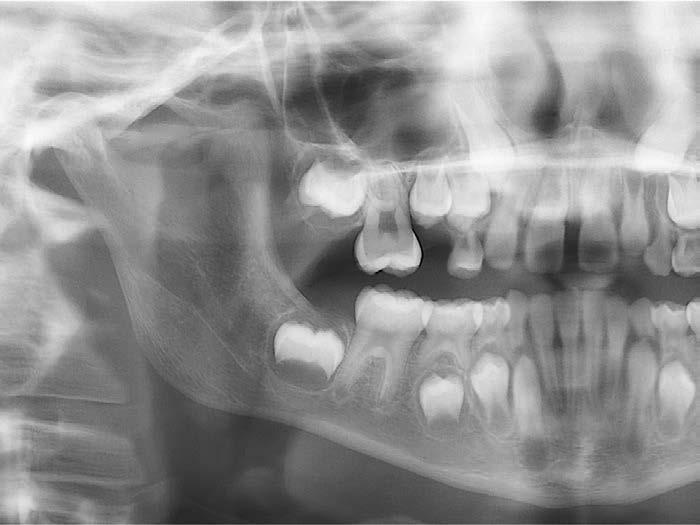

–Corticotomías y Ortodoncia. Ampliando límites del movimiento dental, por la Dra. Aranzazu Senosiain y cols. [50]

–Tratamiento de un caso de Ortodoncia y Cirugía Ortognática con placas preformadas y tecnología 3D, por la Dra. Elena Bonilla Morente y cols. [62]

–Uso del anclaje esqueletal como alternativa eficiente en el manejo ortopédico de clases III por deficiencia de maxilar superior, por el Dr. Carlos Becerra y cols. [74]

–MARPE, una alternativa a la disyunción en el paciente adulto, por el Dr. Enrique Solano y cols. [88]